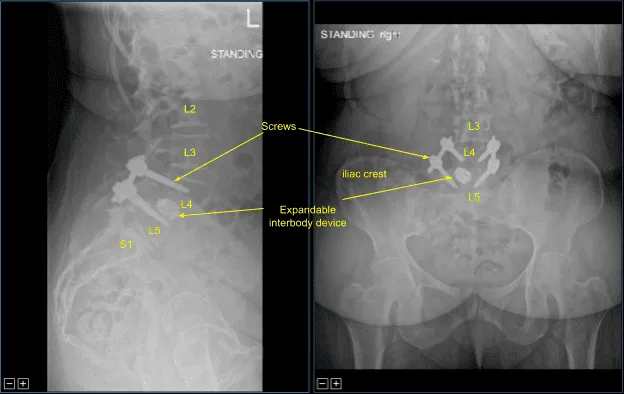

Anterolistesis de L4 sobre L5 con inestabilidad dinámica durante la flexión y extensión

Se realizó una segunda tomografía computarizada intraoperatoria que mostró la correcta posición de todo el hardware e instrumentación implantados. A continuación, se usaron pinzas para determinar la longitud de las varillas de titanio precortadas y predefinidas que se colocaban a lo largo de las cabezas de tulipán bilaterales de instrumentación no segmentaria L4-5 y se aseguraban con tapones de bloqueo.

Estos se tensaron primero en L5 bilateralmente y luego en L4 para lograr la reducción de la espondilolistesis. Se logró una reducción aproximada del 50%. Los tapones de bloqueo se apretaron finalmente con un dispositivo de par y antipar. Luego se retiraron las lengüetas extensoras de los tornillos pediculares. Las heridas fueron irrigadas abundantemente. La hemostasia se confirmó de nuevo.

El paciente hizo un seguimiento dos semanas después de la cirugía y luego continuó en nuestra consulta a las 4, 6, 8, 12 y 24 semanas con radiografías secuenciales. En su última consulta, el paciente declaró que podía realizar sus actividades habituales y que la fisioterapia iba bien.